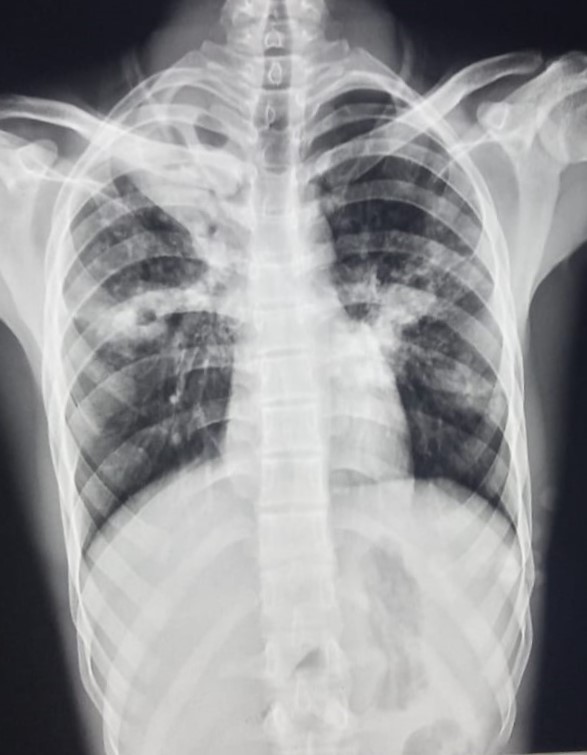

| 4 | IGGMC, Nagpur, Nagpur | P2 | 29-4468 | Moh. Salehuddin | Consent taken on Paper | 68 Yrs. |

Provisional Diag : Miliary TB?

Final Diag : Miliary TB |

TB Case (Confirmed) | Bilateral Infiltrate Query Miliary | Abnormality visible on x-ray |

View |

|||